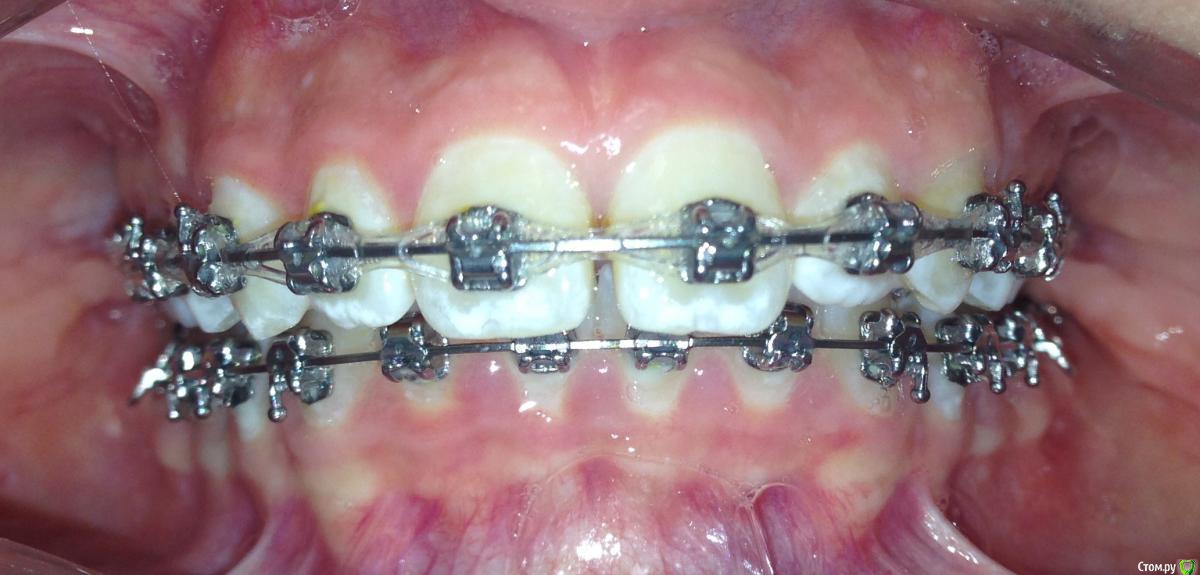

post-38874-0-87186300-1459536185_thumb.jpgpost-38874-0-15339500-1459536188_thumb.jpgpost-38874-0-82577500-1459536190_thumb.jpgpost-38874-0-61079300-1459536193_thumb.jpgpost-38874-0-22178300-1459536196_thumb.jpgpost-38874-0-56404400-1459536198_thumb.jpgpost-38874-0-43380300-1459536199_thumb.jpgpost-38874-0-04081600-1459536228_thumb.jpgpost-38874-0-34503200-1459536230_thumb.jpgpost-38874-0-34236500-1459536233_thumb.jpgpost-38874-0-95387400-1459536234_thumb.jpgpost-38874-0-86290600-1459536242_thumb.jpgpost-38874-0-47956700-1459536252_thumb.jpgpost-38874-0-98507600-1459536273_thumb.jpgpost-38874-0-52220700-1459536283_thumb.jpgpost-38874-0-12327700-1459536263_thumb.jpg

Извините за качество фото.

Пациентка 14 лет. Было принято решение лечить без удаления, тк. профиль не позволяет да и ретропозиция нч. Лечение идет. Я назначила ранние эластики слабые, на 17/25 нити на вч и 18 нити на нч. по 2 классу короткие 3,4-4,5. Пациентка пришла через месяц жалуется на щелканье челюсти во время ношения эластиков и сразу после их снятия. Т.е. если открывает рот, то челюсть скачкообразно двигается и щелчками. Последние 2 недели, когда много говорит, то вообще стала заедать. Это она так сказала. После отмены эластиков (страшно), через неделю пришла, рот открывает ровно, без девиации, щелчков нет. Вопрос: почему щелкает и что с этим делать? По поводу прикуса, посоветуйте, пожалуйста, как нормализовать? Аппарат типа гербста? может ей твинблок сделать? Эластики? К сожалению другими методами я пока что не владею. Спасибо, очень жду ваших советов.